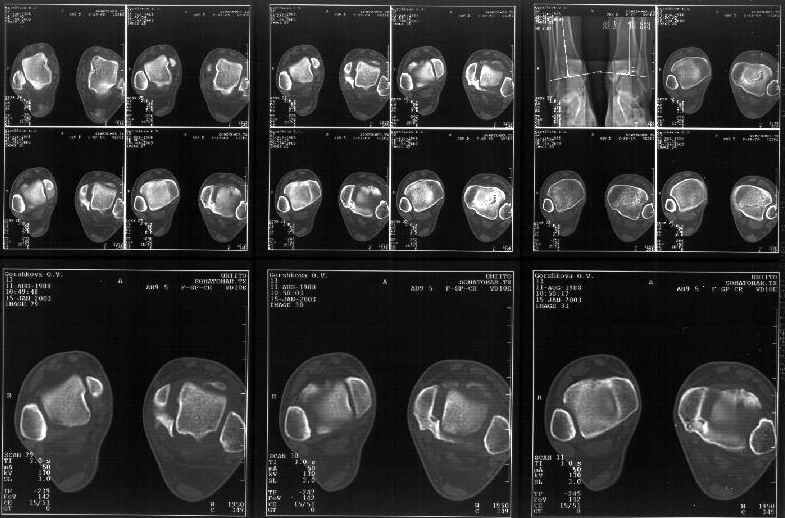

На следующий день пациентке сделали КТ. Может быть, после просмотра картинки будут другие предложения? Не убрать ли ве-таки этот фрагмент

позади внутренней лодыжки, который оттесняет таран кнаружи?

Думаю, КТ прочитан не верно. Задняя часть медиального маллеола, в сущности уже часть заднего маллеола стоит на месте и трогать её не следует. Передняя часть маллеола на 3-4 мм удалена от тарана. Сравните с пространством между

латеральным маллеолом и тараном. В норме все три должны быть одинаковы: между тараном и латеральным, задним и медиальным. Это главное условие устойчивого сидения тарана в голеностопном суставе.

Все-таки она как раз была была отколота и вместе с тараном смещена латерально.

Внутренняя лодыжка не была сломана, она как была на своем месте, так там и находится. Это таран от нее отдавлен кнаружи смщенным в его сторону фрагментом позади внутренней лодыжки. За счет чего и есть проявления нестабильности связок.

Мне в тоже время совершенно ясно видно по той же КТ, по 4 срезам, расположенным в центре и вверху пленки, что перелома внутренней лодыжки не было, в следующем собщении я приложу увеличенный фрагмент томограммы. А к этому письму прилагаю увеличеный фрагмент послеоперационной рентгенограммы, где выделил отколотый фрагмент

позади внутренней лодыжки. И он, как я вижу, находится между стержнем и тараном. А перелома внутренней лодыжки, и тем более смещения, IMHO

не определяется.

Здесь 4 среза, начиная от основания лодыжки и проксимальнее. Где, по Вашему мнению, проходит линия перелома, отделяющая переднюю часть внутренней лодыжки от большеберцовой кости? Заранее спасибо.

Я пометил линию перелома черной линией.

К сожалению на последних присланных срезах КТ нет более низкого, через таран, среза, который был на прежнем майле. На XR я попытался показать

стержень внутри сустава и то как он раскрывает пространство между тараном и мед. малеолом.

Сегодня пациентке сделали сравнительную КТ. А ксиальные и Фронтальные срезы приложены. Ваше мнение?

Фронтальные

Аксиальные

Отправитель: Й. Воск 19 Январь 2003, 22:50

На КТ я попытался изобразить скромными своими способностями (А)- место перелома, (С)- нормальный суставной зазор меж тараном и тремя его маллеолами. (В)- образовавшийся в результате перелома широкий раза в три зазор, позволяющий, по-моему, сублюксацию тарана при ходьбе. В свете данных КТ, критически важных, я бы предложил вертикальную остеотомию места перелома

задне-внутренним подходом и фиксацию мед. маллеола прижатым к тарану с помощью тонкого compression screw. После этого гипсовый сапожок и немедленное расхаживание ноги.